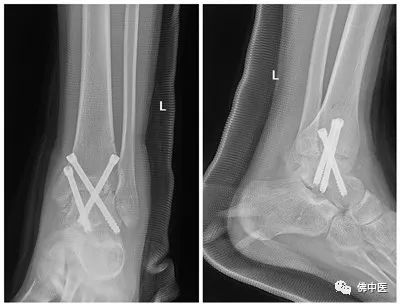

术后X光

术后,足踝专科的护理团队严密监护小李术后伤口情况,每天检测凝血因子活性并及时调整补充。康复医学科医生也在术后第二天按预先制定的计划对小李施行康复训练。术后2周,小李伤口愈合良好,顺利出院。后期小李还需要继续接受进一步的康复治疗。